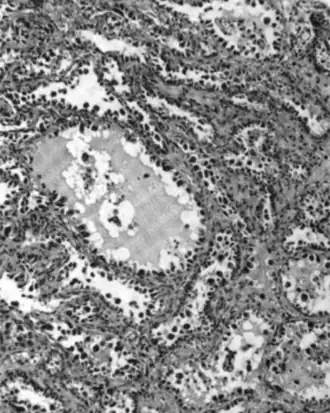

Serous carcinoma

.jpg)

Serous ovarian cancer is the most common type of epithelial ovarian cancer and it accounts for about two-thirds of cases of epithelial ovarian cancer.[28] Low-grade serous carcinoma is less aggressive than high-grade serous carcinomas, though it does not typically respond well to chemotherapy or hormonal treatments.[28] Serous carcinomas are thought to begin in the Fallopian tube.[70][71] High grade serous carcinoma accounts for 75% of all epithelial ovarian cancer.[69] About 15–20% of high grade serous carcinoma have germline BRCA1 and BRCA2 mutations.[69] Histologically, the growth pattern of high grade serous carcinoma is heterogenous and has some papillary or solid growth patterns.[69] The tumor cells are atypical with large, irregular nuclei.[69] It has a high proliferation rate.[69] 50% of the time, serous carcinomas are bilateral, and in 85% of cases, they have spread beyond the ovary at the time of diagnosis.[72]

Serous Tubal Intraepithelial Carcinoma (STIC) is now recognized to be the precursor lesion of most so-called ovarian high-grade serous carcinomas.[72] STIC is characterised by

- Abnormal p53 staining

- Ki67 proliferation index in excess of 10%

- Positive WT1 (to exclude metastases)[72]